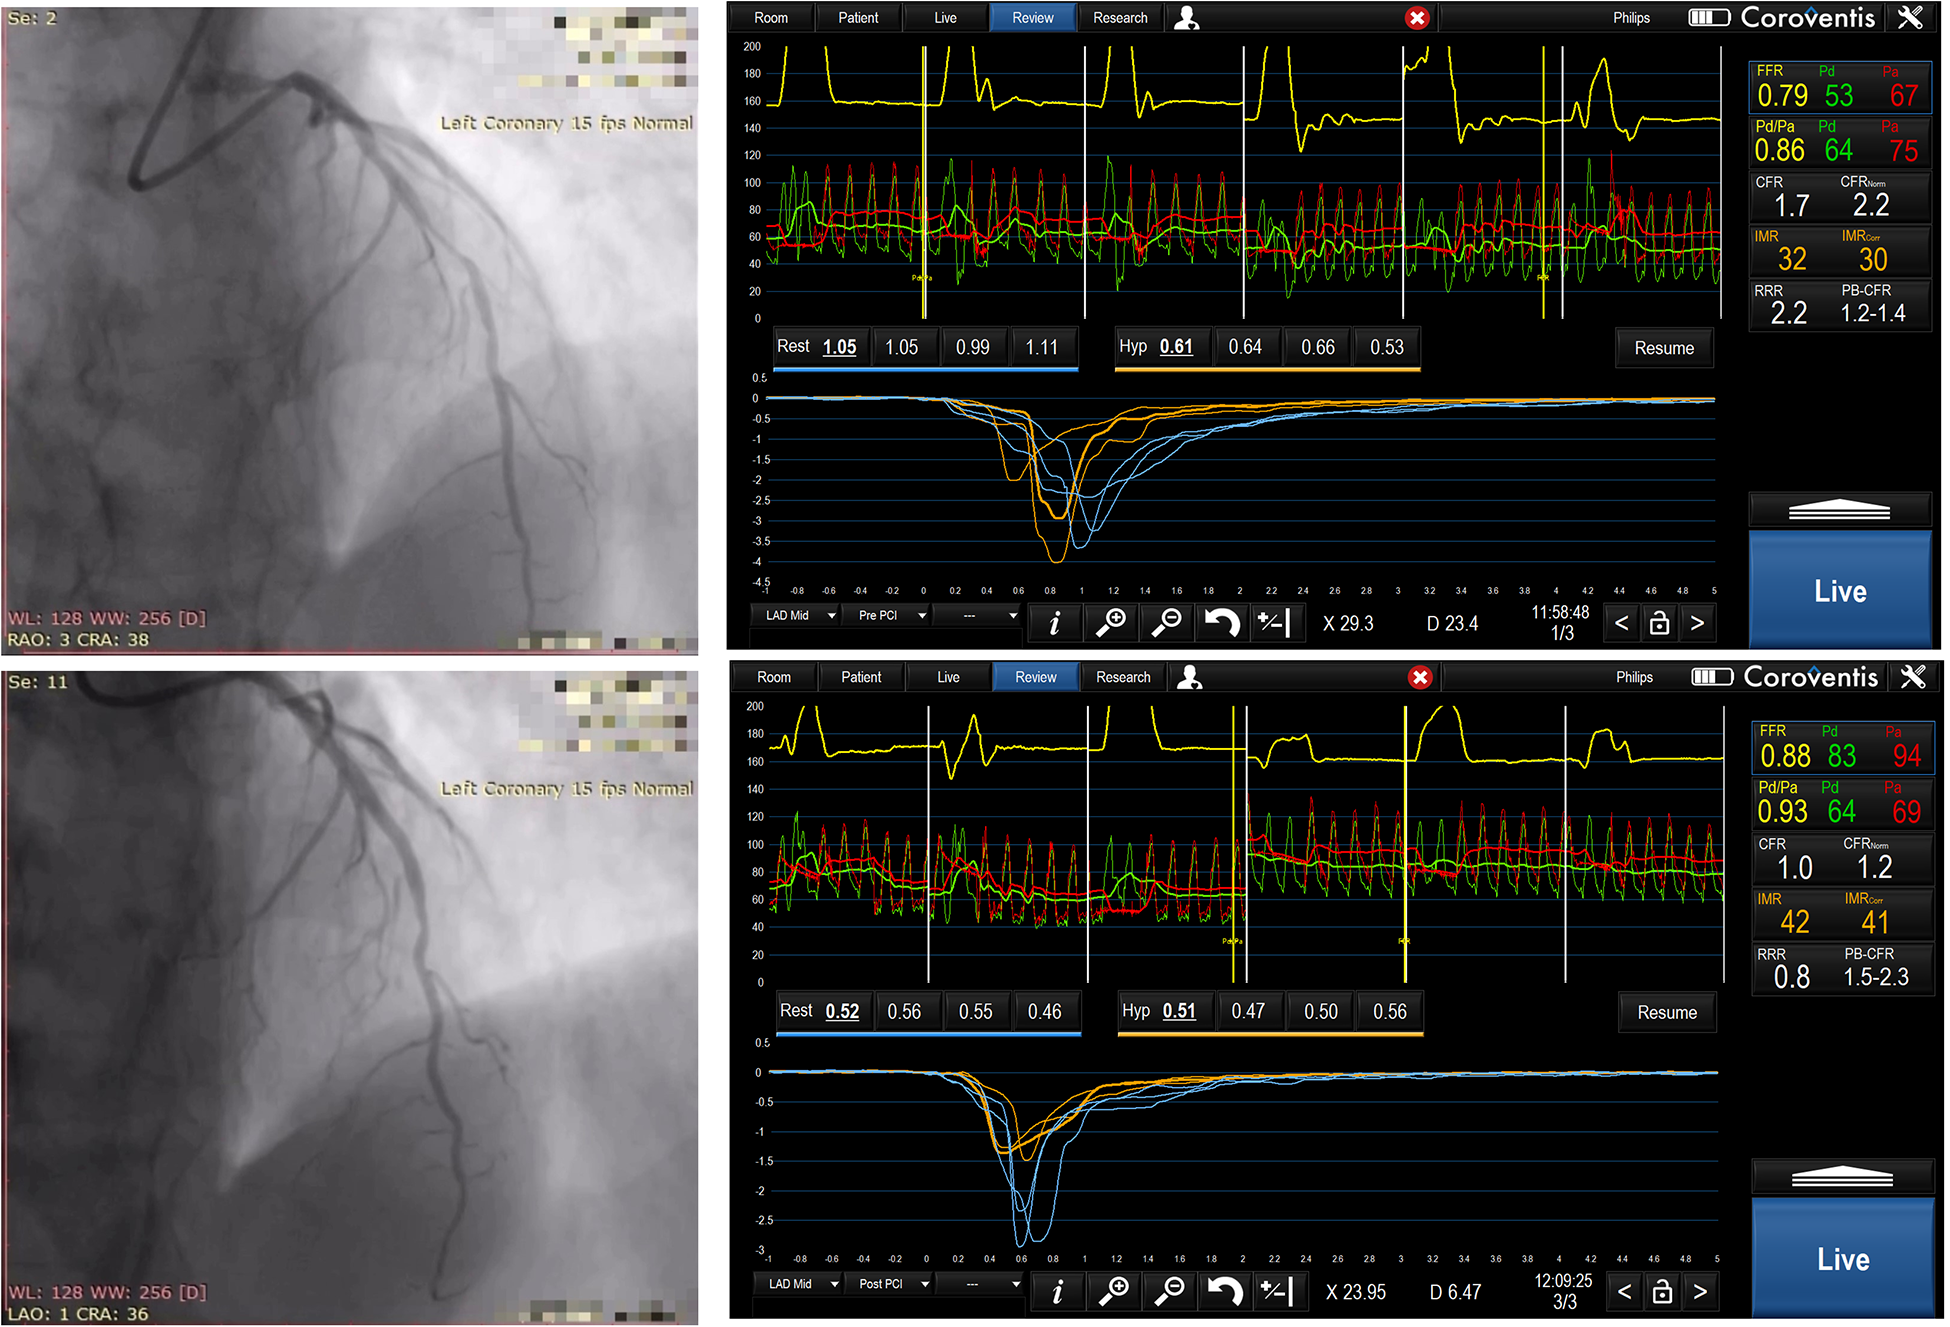

Figure 1

Sixty-two years old male, randomized to TMZ -, predilatation with 2.5 × 15 mm non compliant balloon, then drug eluting stent 3.0 × 24 mm was implanted in mid LAD. Angiographic images and physiology measurements before and after PCI were shown, please note high IMR and low CFR values.